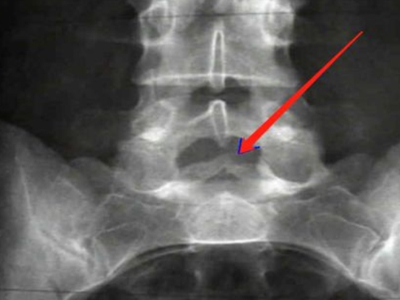

骶1隐性脊柱裂的图

骶1隐性脊柱裂主要是在身体发育的时候骶1的椎板未达到融合,在影像图上可以发现棘突缺如、椎板缺如的表现,需要通过手术进行治疗。